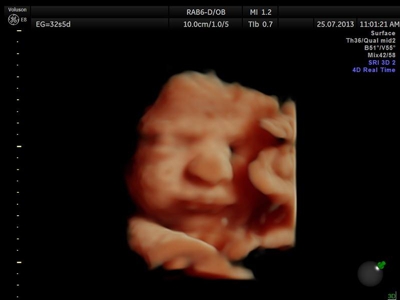

La ecografía 4D HD/5D consiste en la adquisición y presentación continúa de volúmenes. La denominación de la técnica obedece a que hay cuatro dimensiones involucradas: ancho, largo, profundidad y tiempo.

Si bien la Ecografía 4D HD/5D puede realizarse en cualquier etapa del embarazo, recomendamos realizarla entre las semanas 24 a 32 de gestación ya que se pueden observar rasgos bien definidos en el bebe.

Fotografías de ecografías 4D HD/5D

Haga click sobre las imágenes para ampliar